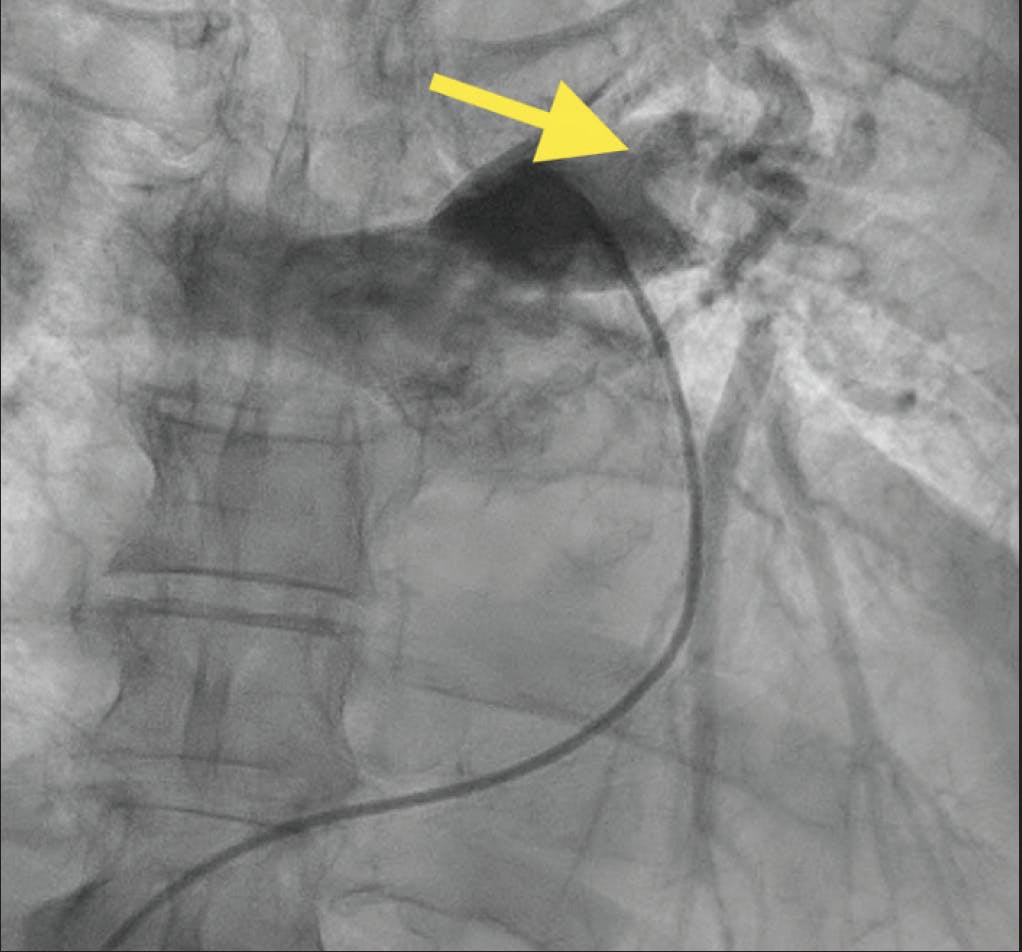

In the emergency department, she was tachycardic at 120 bpm with a systolic blood pressure of 100 mm Hg. She required 40% high-velocity oxygen support and was assessed as clinically unstable. Echocardiography revealed a hyperdynamic left ventricle, a dilated right ventricle with moderately to severely reduced function, and McConnell sign, consistent with PE (Figure 1). CTA showed a high RV/LV ratio of 1.4 and extensive left PE with possible saddle thrombus (Figure 2). The patient became progressively unstable and was administered thrombolytic therapy with tissue plasminogen activator. Overnight, her oxygen requirement improved to 6 L via nasal cannula, although she remained dyspneic and relatively hypotensive. Intravenous heparin was continued, and she was referred to interventional cardiology for further management with CAVT using Penumbra’s Lightning Flash 2.0.

Figure 2. CT revealing high RV/LV ratio of 1.4 and extensive PE with saddle thrombus.